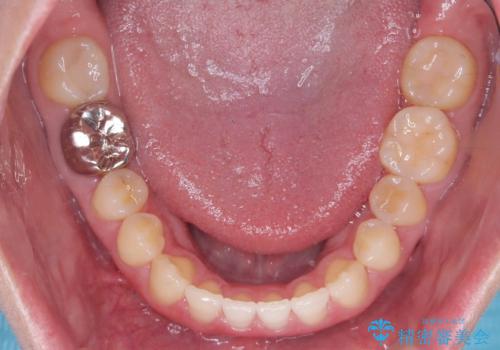

すきっ歯・切端咬合・空隙歯列|インビザラインで11ヵ月で治療完了

- すきっ歯と切端咬合(上下の前歯が先端で当たるかみ合わせ)を主訴にご来院された患者様です。

矯正検査を行った結果、非抜歯でインビザラインによる治療が可能と判断し、マウスピース矯正で改善を行いました。

11ヵ月で矯正治療が終了し、前歯の隙間も改善、見た目とかみ合わせも良好な状態となり、患者様にも大変ご満足いただけました。